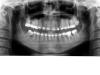

Dina Опубликовано 26 декабря, 2006 Поделиться Опубликовано 26 декабря, 2006 Уважаемые врачи нужна хоть какая-то помощь. Брекеты на в/ч стоят с января 2005, на н/ч с мая 2005, было удалено немеренно зубов, теперь думаю , что зря вот фото здесь, не очень качественно, но... http://foto.mail.ru/mail/denkorzik/ перед лечением были удалены три восьмерки, одна видна вверху слева полупроросшая, была удалена 6 вверху слева на ее место поставили 7 и начала расти 8, вверху справ удалена 4 внизу удалены 5 слева и 6 справа не было с 1999 года, то естсь 7 стоял отдельно, я теперь понимаю, что нижн. прав. 8 удалять не надо было, но что я могла не доверять врачу? тем более тогла я была вообще бараном относительно стоматологии и ортодонтии. Мой ортодонт решил тянуть эту 7 на место 6 - видно, на снимке, что 7 завалена и сейчас она в язычном положении, ткань то рассосалась... короче ужас во всем, я не знаю, где найти в Киеве хорошенго ортодонта, я была на консультации у 4 и все несли бред, один вообще предложил лицевую дугу с тягой в виде шапочки, а мне 28 лет. вот рентген, сделанный три дня назад мне не наравятся верхние единицы и двойка правая, о нижних вообще молчу. мой ортодонт предлагает все это решить при помощи трейнера для брекетов. посоветуйте, что мне делать далее, я настроена менять ортодонта, но кто ж за такое произведение возмется. Спасибо. Ссылка на комментарий

Orthodoc Опубликовано 26 декабря, 2006 Поделиться Опубликовано 26 декабря, 2006 Уважаемые врачи нужна хоть какая-то помощь. Брекеты на в/ч стоят с января 2005, на н/ч с мая 2005, было удалено немеренно зубов, теперь думаю , что зря вот фото здесь, не очень качественно, но... http://foto.mail.ru/mail/denkorzik/ перед лечением были удалены три восьмерки, одна видна вверху слева полупроросшая, была удалена 6 вверху слева на ее место поставили 7 и начала расти 8, вверху справ удалена 4 внизу удалены 5 слева и 6 справа не было с 1999 года, то естсь 7 стоял отдельно, я теперь понимаю, что нижн. прав. 8 удалять не надо было, но что я могла не доверять врачу? тем более тогла я была вообще бараном относительно стоматологии и ортодонтии. Мой ортодонт решил тянуть эту 7 на место 6 - видно, на снимке, что 7 завалена и сейчас она в язычном положении, ткань то рассосалась... короче ужас во всем, я не знаю, где найти в Киеве хорошенго ортодонта, я была на консультации у 4 и все несли бред, один вообще предложил лицевую дугу с тягой в виде шапочки, а мне 28 лет. вот рентген, сделанный три дня назад мне не наравятся верхние единицы и двойка правая, о нижних вообще молчу. мой ортодонт предлагает все это решить при помощи трейнера для брекетов. посоветуйте, что мне делать далее, я настроена менять ортодонта, но кто ж за такое произведение возмется. Спасибо. У Вас не закончено ортодонтическое лечение. Остались неразвернутые зубы, при улыбке по-разному видны правые и левые резцы. О прикусе судить сложно, т.к. не видны боковые группы зубов при смыкании. Серьезная проблема с нижним моляром, по снимку оно находится в мягких тканях, выраженные пародонтальные карманы. Трейнер для брекетов в вашем случае не поможет, лечение нужно заканчивать на брекетах, лицевая дуга у взрослых пациентов тоже не эффективна. К сожалению, ортодонтов из Киева не знаю, но Вам лучше сменить доктора. Ссылка на комментарий